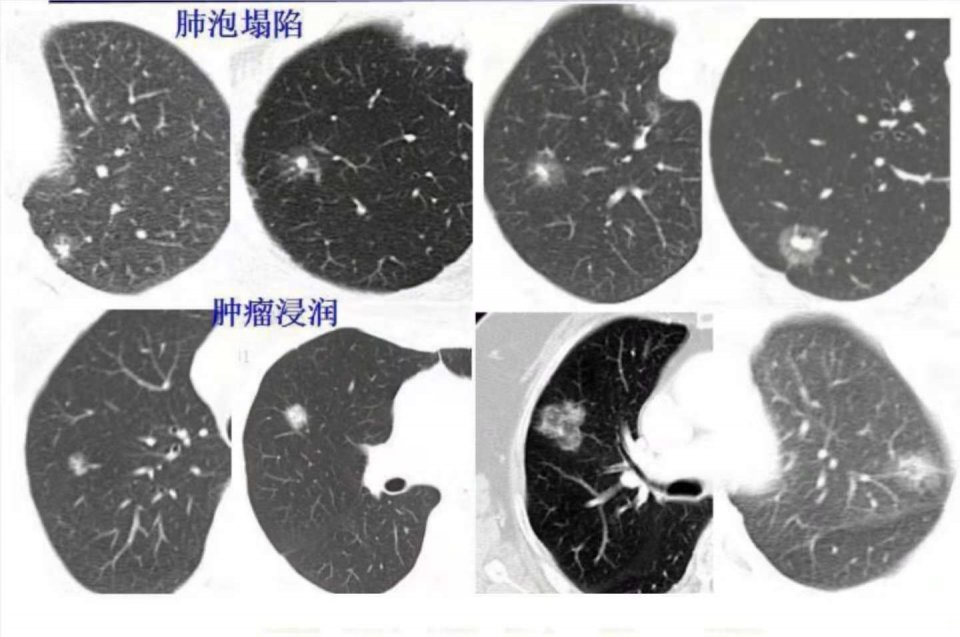

上面这8个肺癌病人,都是胸部体检及时发现并治愈的(本组病例来自浙江舟山肺癌多学科研究中心)。